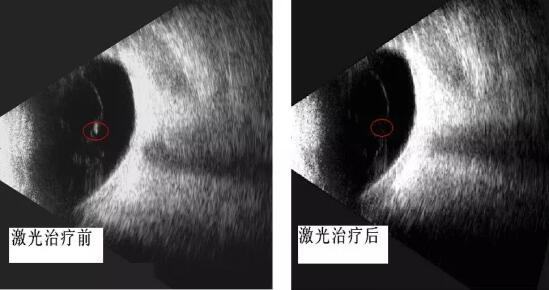

啄木鸟 眼科开启"灭蚊"时代 ――飞蚊症的治疗